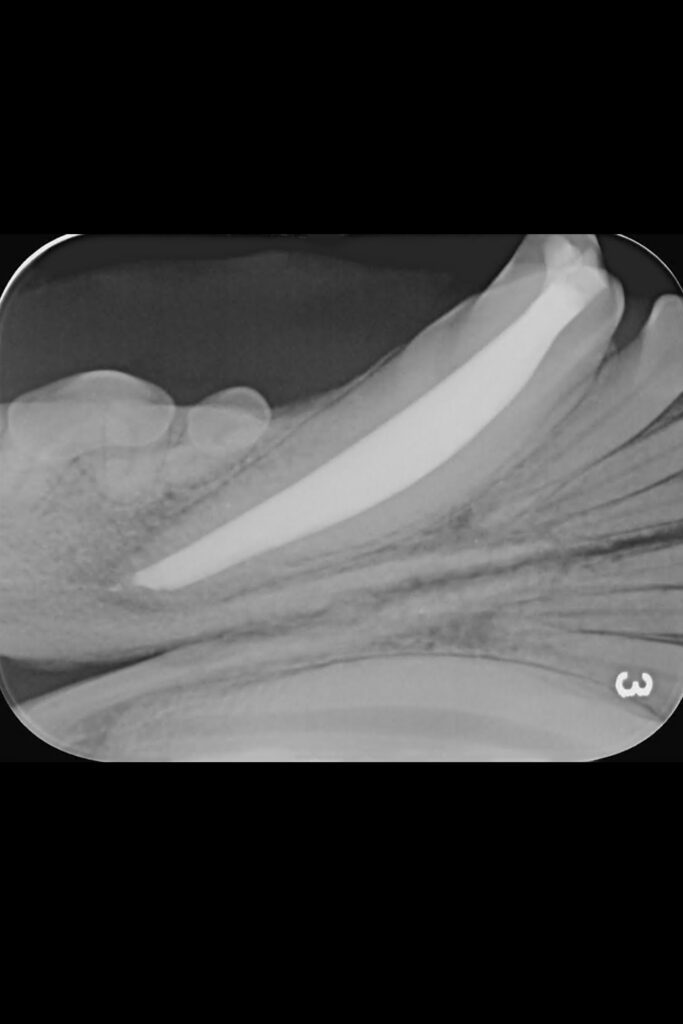

Max’s dental radiographs for his fractured mandibular canine tooth

Radiography Assistant Ellie brought her lovely Labrador Max in to see dentist Hannah after he fractured his lower canine tooth.

Initial radiographs were taken on our intraoral dental-specific X-ray unit to evaluate the dense tooth and bone structure. This revealed what was happening within the tooth and beneath the gumline – all the areas that cannot be seen with a visual examination. These showed not only the crown fracture but also a wide pulp chamber, which required root canal treatment.

A key part of this treatment involves inserting increasing file sizes into the tooth to reach the pulp to remove any infected or necrosed tissue. X-ray images are then again taken at various points throughout the procedure to check file size and position.